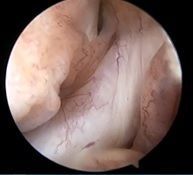

![]() ![]() | ![]() ![]() | ![]() ![]() |

| ACLは緊張がなく機能していない | 内側半月板は異常なし | 外側半月板は異常なし |